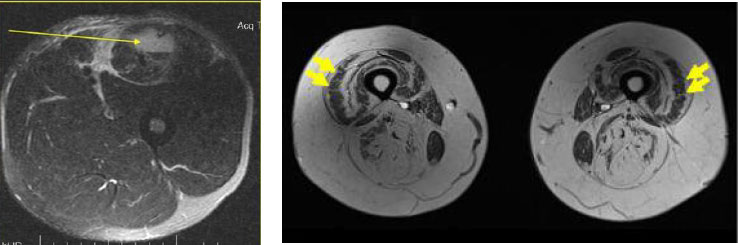

Посмотрите на срез бедра, который сделан с помощью МРТ.

Слева нормальная, тонусная мускулатура в бедре, справа жировое перерождение мышц (мышцы просто отсутствуют). Нормального кровообращения в таких мышцах просто не будет, так как мышц нет. Скорее всего будет варикоз. Жировая мышечная дистрофия не редкость, когда речь идет о полном отсутствии нагрузки (она должна быть!) на скелетную мускулатуру.